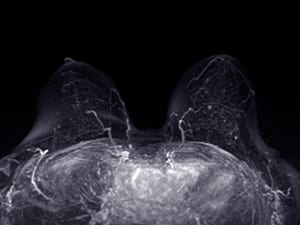

The MRI Question: Seeing More vs. Doing Better

In a different clinical space—diagnostic imaging before surgery—Isabelle Bedrosian, MD, a surgical oncologist and professor of breast surgical oncology at The University of Texas MD Anderson Cancer Center, led a randomized phase III trial that investigated what impact preoperative breast MRI has for patients with stage 1 or 2 HR-negative breast cancer who are eligible for lumpectomy. Bedrosian explained that MRI is commonly included because it can detect disease not seen on mammography, but MRI often leads to additional testing, surgical delays, and increased financial burden.

She noted that those costs and delays would merit acceptance if MRI were linked to better outcomes but emphasized that its impact on such outcomes has been understudied. Bedrosian and colleagues designed the Alliance A011104/ACRIN 6694 clinical trial to test whether detecting and removing mammographically occult disease by MRI reduces local recurrence and improves locoregional control.

The study enrolled 319 patients who did not have an inherited BRCA1 or BRCA2 gene mutation, did not have cancer in both breasts at the same time, and had no history of prior breast cancer. All had diagnostic mammography with or without ultrasound, then were randomized to receive or forego additional imaging by MRI. After a median follow-up of 61.1 months, 93.2% of the 161 patients in the MRI arm were free of locoregional recurrence at five years, compared with 95.7% of the 158 patients in the no-MRI arm—a difference she described as not statistically different.